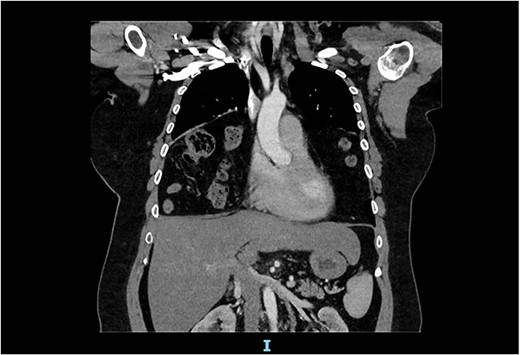

The spirometry results from her General Practitioner showed a restrictive pattern with FVC of 2.08L (55% predicted), FEV1 of 1.62L (54% predicted) and FEV1/FVC ratio of 0.78 (96% predicted). Her chest X-ray demonstrated a large hiatus or congenital hernia (Fig. 1). Subsequent computed tomography (CT) of the chest, abdomen and pelvis showed a large 88 × 48-mm defect of the anterior diaphragm consistent with MH. Hernial contents extended to the superior mediastinum and were primarily large bowel and omentum, with no intestinal obstruction (Figs 2–4).

Arterial contrast CT of the chest. Sagittal slice in the midline of the body. The diaphragmatic defect is clearly seen anteriorly, and the abdominal contents are seen extending to the superior mediastinum.